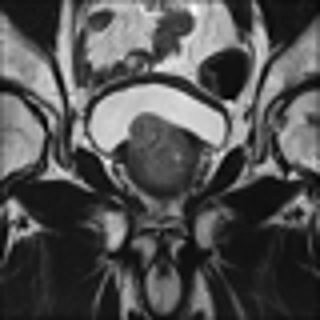

Refer to caption

(a) Bicubic interpolation

(b) Sparse Representation

(c) SRCNN

(d) SRResNet

(e) SRGAN 4x

(f) HR ground truth image

Figure 4: SR result for 4×4\times upscaling using- Bicubic interpolation, SRCNN, Sparse Representation, SRRestNet, and SRGAN

V-C Qualitative SRGAN Image Quality Assessment

Fig. 4 contains an example SR output for each method and the LR and HR images for reference. The LR image is severely pixelated and has no edge fidelity. While the image produced via bicubic interpolation has no pixelation, this method is still unable to preserve the high frequency information found in the ground truth image. The Sparse Representation method produces slightly better results than the previously discussed methods. However, the large amount of space and time overhead required by this model precludes it from clinical use. The SRCNN begins to show edge preservation, however the features within different regions of the output SR image are smoothed out. The SRCNN is especially biased toward smoothing the image because the network only uses MSE loss. The SRResNet has both MSE and perceptual loss yet fails to outperform the SRGAN. Clearly, the discriminator network seeks out the high frequency information that differentiates HR and LR images, thus forcing the SRGAN output to have far more high frequency details than the output of the SRResNet. The SRGAN 8x network is not able to maintain as high an edge fidelity as the SRGAN 4x network. This result is expected because the SRGAN 8x network is provided with far less information since the input LR image is a further 2x smaller in both dimensions (Fig. 5). Overall, in comparing the SRGAN to the other models, the outputs from the SRGAN are visually closer to the original HR ground truth images.